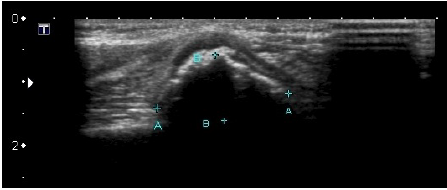

Criança de 5 anos, feminina, apresenta no exame físico área de entumescimento de partes moles no aspecto medial do terço proximal do úmero esquerdo com sinais de estar fixa aos planos profundos e livre em relação à pele e ao subcutâneo, sem sinais flogísticos e quase indolor.

Segue-se imagens de US e Rx do segmento corpóreo.

O quadro clínico e imagenológico sugere